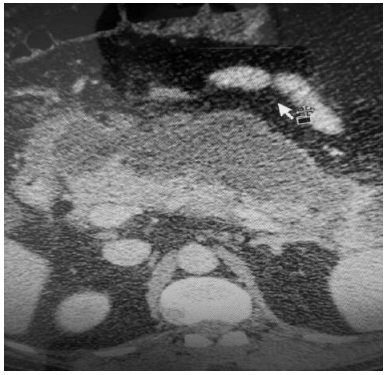

Um paciente de 78 anos de idade queixa-se de dor abdominal aguda em epigástrio e flanco direito há vinte dias. Já procurou dois serviços anteriormente, sendo que, no primeiro, ficou internado por cinco dias e recebeu o diagnóstico de colecistite aguda e, no segundo, foi observado um problema no pâncreas (SIC). Não tem consigo nenhum documento oficial. Chegou ao pronto-socorro com dor em epigástrio (4/10), desidratado, descorado, anictérico e afebril. Apresentava massa palpável em epigástrio,sem sinais de irritação peritoneal. Exames laboratoriais revelaram: hemoglobina de 11 mg/dl; leucócitos de 14.000; glicemia de 108; amilase de 92; e lipase de 72. Realizou, também, a tomografia abdominal com contraste mostrada no corte abaixo.

Com base nesse caso hipotético, assinale a alternativa correta.